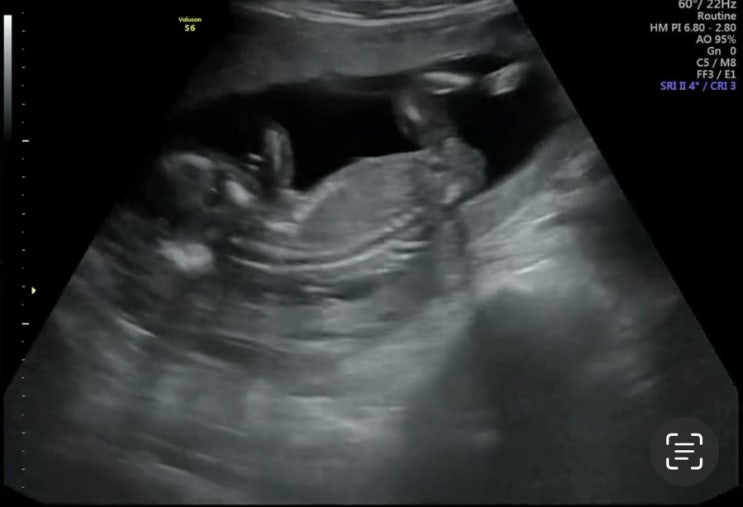

7. 대구 수성구 더블유여성병원(#7. 17주 1일 초음파진료) 및 (16주 치과치료, 17주 임신증상) 후기

2024년 6월 11일 화요일 - 15주에 병원을 다녀왔었고 4주뒤인 19주에 정기진료일이나... 잘있는지(당연히 ...